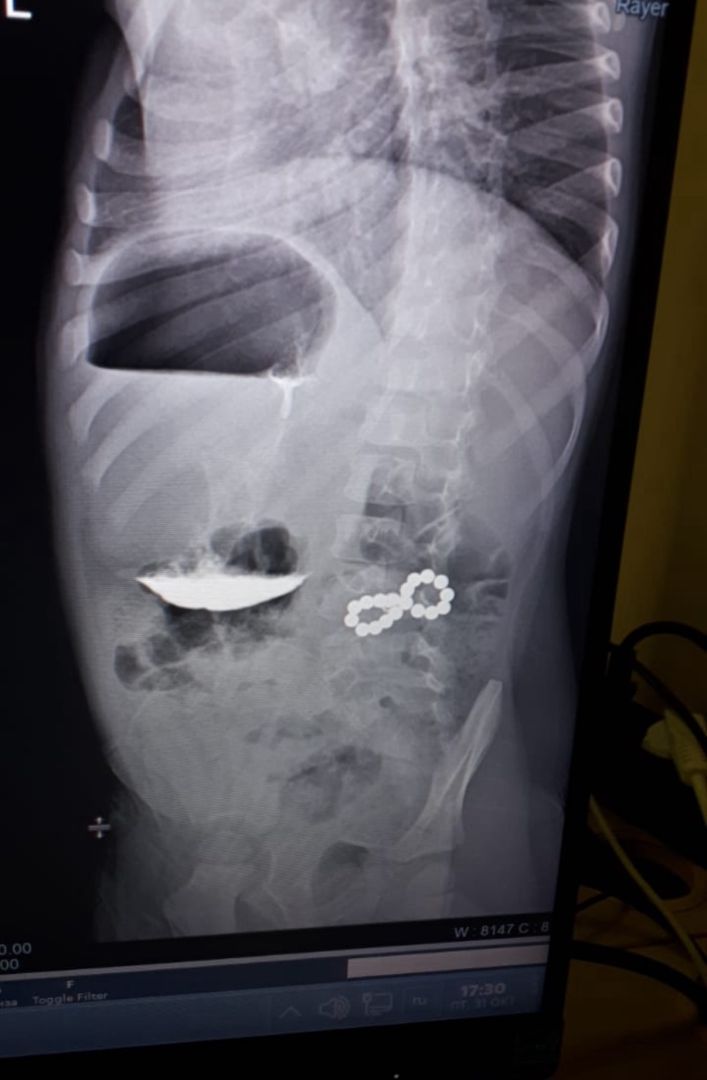

• Ставропольские хирурги спасли трехлетнего мальчика, проглотившего 18 магнитов

Врачи ставропольской краевой детской больницы провели экстренную операцию трехлетнему мальчику. Из его кишечника извлекли 18 магнитов, рассказали в пресс-службе медучреждения.

Ребенок поступил в больницу с жалобами на кашель. На рентгене специалисты увидели инородные тела в пищеварительной системе. В таком случае требуется срочная операция. Магниты, оказавшись в разных участках кишечника, притягивались друг к другу с большой силой, сдавливая стенки органа. Это грозило некрозом тканей, перитонитом и серьезными осложнениями.

Хирургическое вмешательство прошло успешно. Из двенадцатиперстной и толстой кишки извлекли 18 магнитов. В операции участвовали хирурги Быков Н.И. и Ячная О.И., анестезиолог Айдабекова Э.А., операционная сестра Парфенюк В.В. и медсестра-анестезист Алиханова З.К.

Фото: социальные сети Ставропольской краевой детской клинической больницы